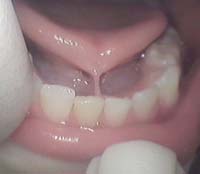

+Lưỡi dính (Ankyloglossia) :

• Thường hay đi với dị tật lưỡi chẽ (Tongue bifurcation) làm cho đầu lưỡi không nhọn mà bị chẻ làm đôi. Thắng lưỡi nằm ở sán miệng, nối sàn miệng với sàn lưỡi và thân lưỡi. Trong trường hợp bệnh nhân có thắng lưỡi to , bám dính vào phía chóp lưỡi và đầu lưỡi, lưỡi bị co kéo cử động của lưỡi bị hạn chế, không còn linh hoạt, đưa ra trước và hai bên rất khó khăn. Bệnh nhân có lưỡi bị dính sẽ khó khăn trong phát âm , giọng nói bị ngọng nghịu và khi nuốt lưỡi co lại khó khăn. Lưỡi có thắng lưỡi dính phải làm phẫu thuật, cắt bỏ thắng lưỡi để giải phóng cho lưỡi, điều quan trọng là phụ huynh phải phát hiện sớm con của mình có dị tật trên và BS RHM khi khám bệnh phải phát hiện được dị tật.